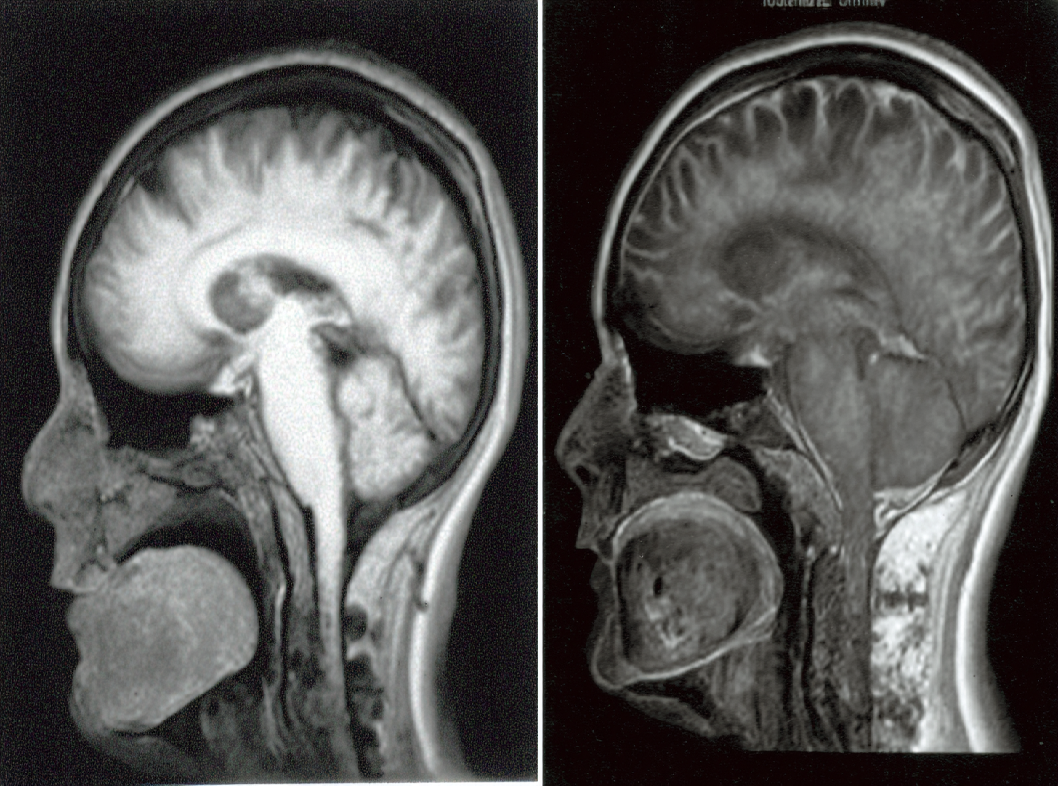

- Аденома гипофиза. Наиболее частой причиной болезни Иценко-Кушинга является наличие опухоли (аденомы) в гипофизе — маленькой железе, расположенной в головном мозге. Эта опухоль стимулирует избыточное выделение адренокортикотропного гормона (ACTH), который, в свою очередь, стимулирует кору надпочечников производить избыточное количество кортизола.

- Образовательные методы. Магнитно-резонансная томография (МРТ) или компьютерная томография (КТ) могут использоваться для визуализации гипофиза и надпочечников, а также для выявления возможных опухолей.

Если опухоль в гипофизе является причиной болезни Иценко-Кушинга, хирургическое удаление опухоли может быть рекомендовано. Это может выполняться с использованием технологии эндоскопии, что позволяет минимизировать повреждение окружающих тканей.